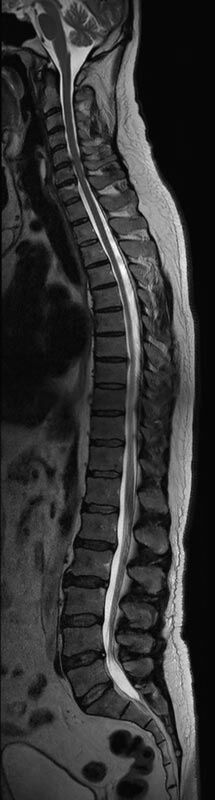

Wirbelsäule

• Abklärung Bandscheibenvorfall

• Beurteilung Einengung des Rückenmarkkanals oder der Neuroforamina im Rahmen der degenerativen Wirbelsäulenerkrankung

• Tumor-/Entzündungsdiagnostik

• Multiple Sklerose

• Abklärung Spondylolisthesis

• Frakturdiagnostik (Alter und Ausdehnung der Fraktur) z.B. im Rahmen der Osteoporose